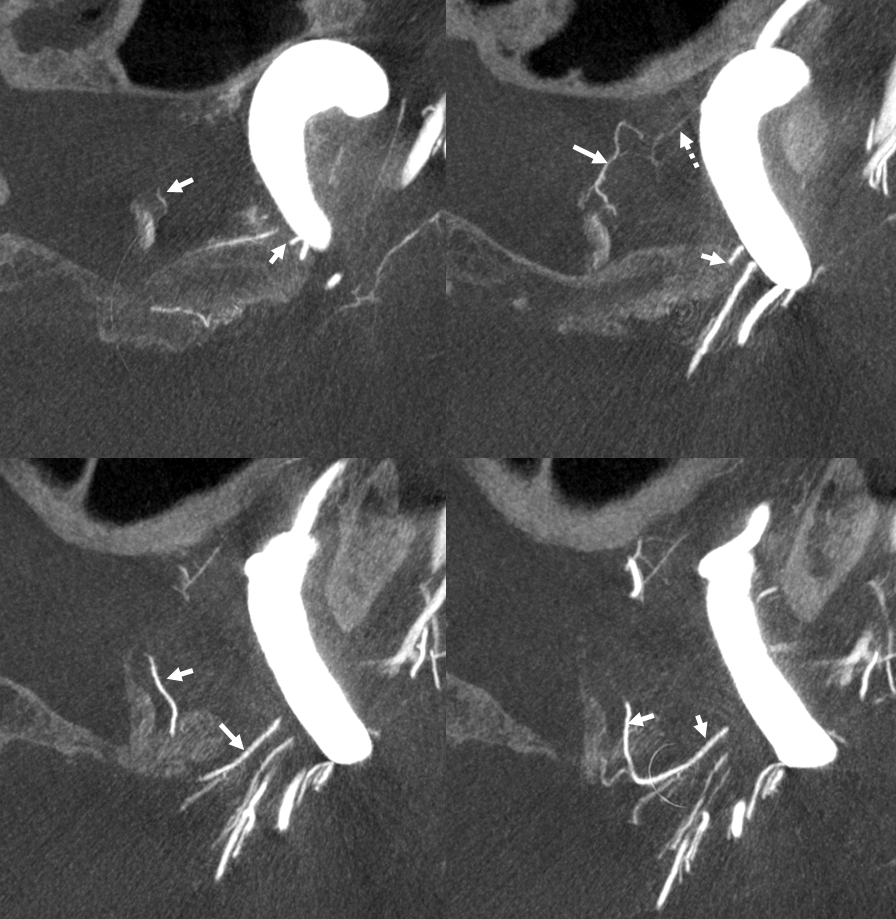

As always neuroangio is about balance. There may be one or more superior hypophyseal arteries. Usually one is visible by cone beam/flat panel CT. Sometimes more than two. Here there are 3. Nicely shown is supply of the stalk (open arrow). There is also likely contribution to the optic chiasm, which is of course very important. The inferior hypophyseal branches (dashed arrow) from the MHT support the posterior pituitary. The ILT is hypoplastic, with lateral branches of the MHT (white arrowhead) heading towards the meckel cave and the recurrent branch along the tentorial edge (black arrowhead) supplying territory normally done by the ILT

Without labels